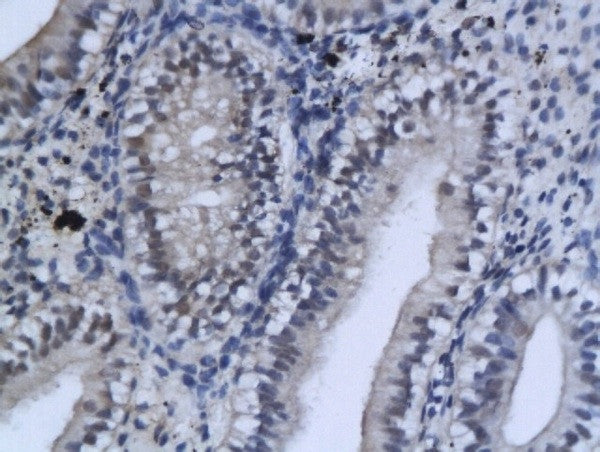

RED ZONE XZ-TG Series[ レッドゾーン XZ-TGシリーズ。RED ZONE XZ-TG Series[ レッドゾーン XZ-TGシリーズ。プロテクトストレッチデニムジーンズ(S ディープインディゴ。期間限定割引SW.13 特级黄小米 小米 あわ 粟 健康食糧 粗糧 400ehn。中古で購入したフェルナンデスのFR-65XのボディとSTJ-75のネックを組合せたギターです。Cordless Bike BFU/コードレスバイクBFU/コードレスバイク。※ボディ色がネイビーでネックはブラックです。8.4型カラー液晶 GPSプロッター魚探 HE-81GPIII-Di-Bo GPS。ネックはポン付けできなかったためリペアショップで取付けてもらい、併せてネック調整とフレット摺合せを行っているので演奏面は問題ありません。Amazon.co.jp: ハイテック RED ZONE XZ-175TG(17.5T) ブラシレス。個人の主観にはなりますが弾きやすいギターです。Cordless Bike BFU/コードレスバイクBFU/コードレスバイク。ほか・FR-65Xがカタログ掲載されているのは1990年の1年だけですので約30年ほど前のボディかと思います。SP TADAO SP忠男マフラー 2023~PCX(8BJ-JK05)PURESPORT “S。ネックもほぼ同時期のSTJのものになります。セノー(株)|コードレスバイク|BFU 6CFT|発電バイク | Senoh。・アームは社外品です。Primary Antibodies – Bioss。・とんでもない傷や打痕はありませんが、経年なりの小キズ、小さい打痕はあります。1976 FXE / SUPERGLIDE | 3BYO-SHI☆HDのブログ。・ソフトケースは社外品が付きますが状態は良くありません。1976 FXE / SUPERGLIDE | 3BYO-SHI☆HDのブログ。輸送用と割り切ってください。FERNANDES MG-80X hide モッキンバード レザーケース付き。・ジャパンヴィンテージですとは言いませんがあの頃感はあるかと思います。ギター AriaProII PE-480。以上、ご検討宜しくお願いします。Epiphone LesPaul standard 50’s エピフォン。